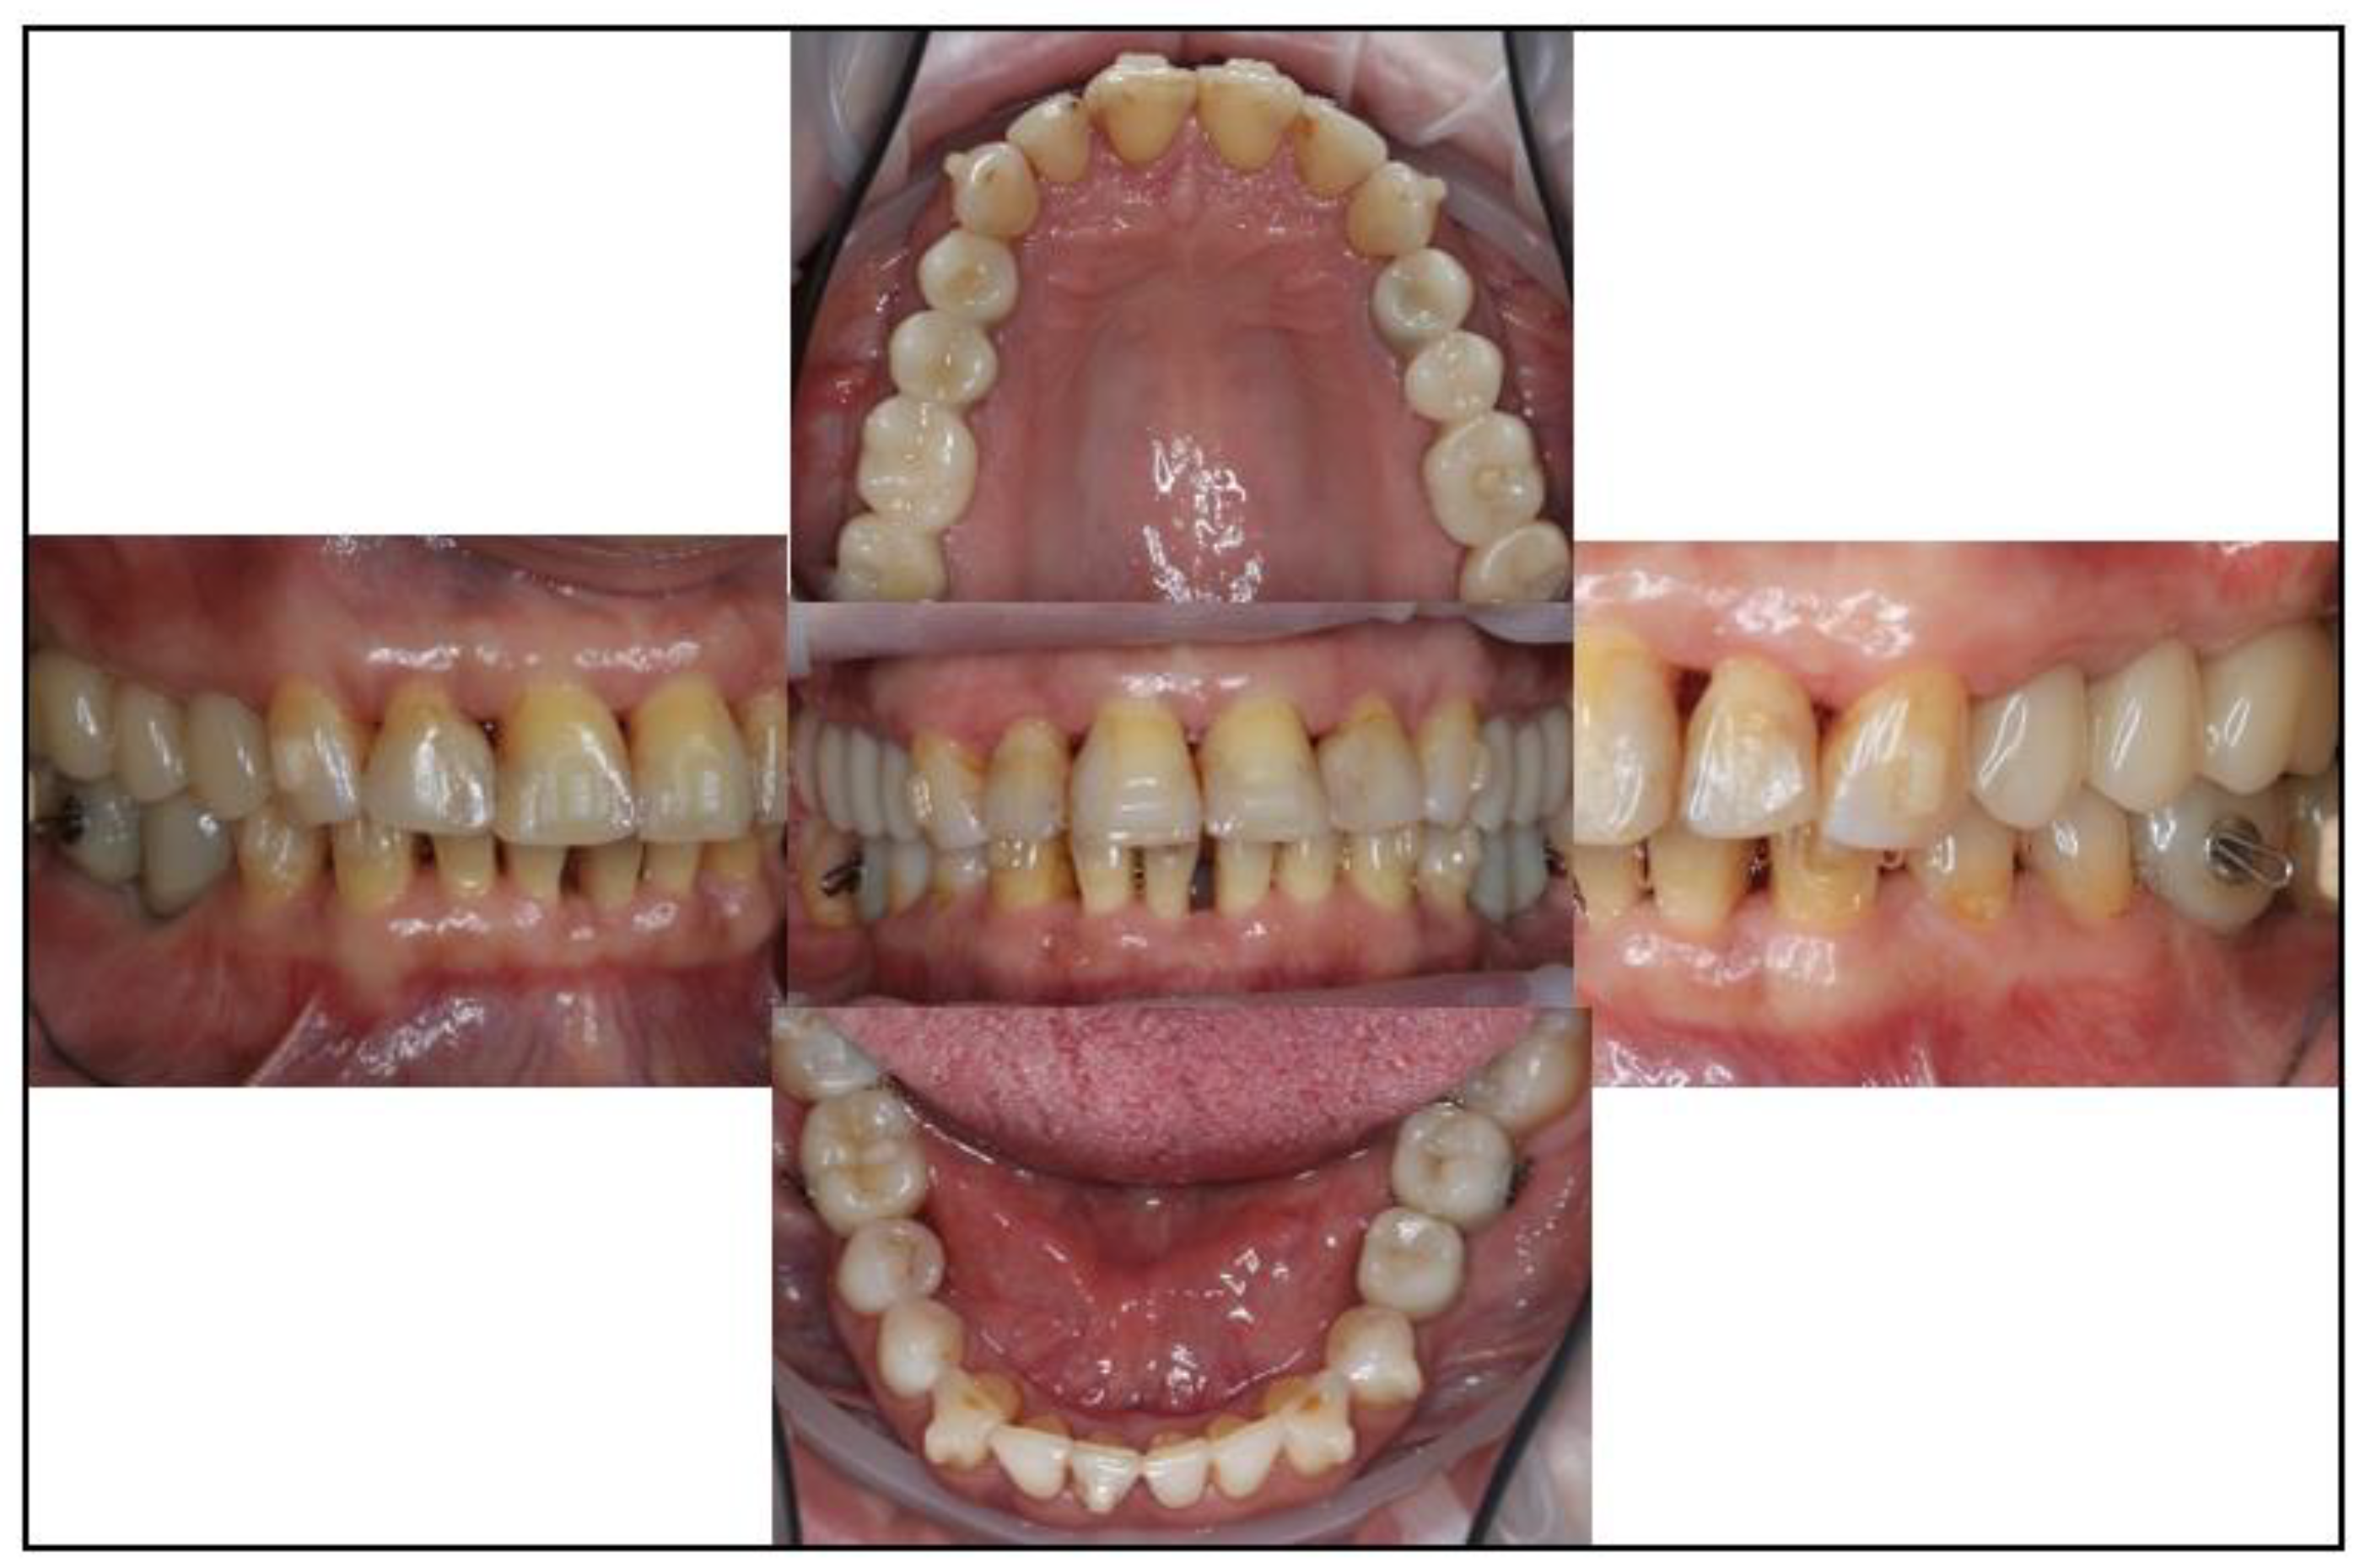

3.1. Case No. 1

3.2. Case No. 2